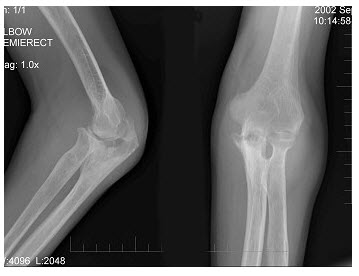

213、单项选择题

女,41岁,纺织工,腕部疼痛无力数周,结合CR和MR,最可能的诊断是()

男,15岁,畏寒,高热2周,摄片如图所示,下列描述正确的是()

A.骨质广泛性溶骨性破坏

B.少许骨质增生硬化

C.大量层状骨膜增生

D.以上描述均正确

E.以上描述均不正确

女,1岁10个月,右肘部外伤,如图所示,最佳的诊断为()

A.全骺分离

B.肱骨髁上骨折

C.肱骨髁上骨折并肘关节脱位

D.内上髁骨骺损伤

E.内上髁骨骺损伤并肘关节脱位